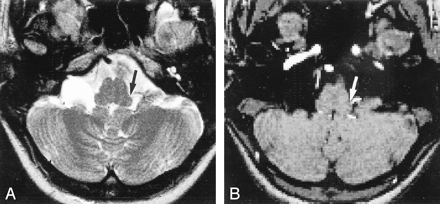

49-year-old man with essential hypertension.

A and B, Axial TSE T2-weighted MR image (A) and MR angiogram obtained with a 3D-TOF sequence (B) show compression of the left ventrolateral medulla by the left vertebral artery with displacement of the brain stem (arrows) (grade III).